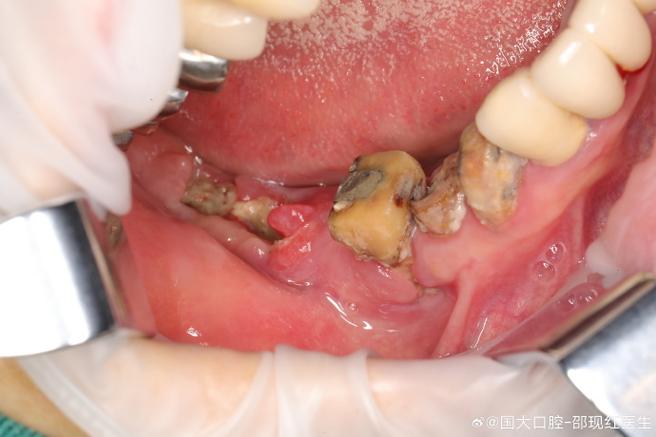

- 这是种植牙最需要关注的长期并发症。 它类似于天然牙的牙周炎,是种植体周围支持组织的炎症和破坏。

- 潜在风险: 如果种植体周围炎长期得不到有效控制,会导致持续的慢性炎症状态。理论上,长期的慢性炎症刺激(无论发生在口腔哪个部位)可能是癌症发生的一个促进因素,需要强调的是:

- 这种关联在种植体周围炎患者中极其罕见。

- 口腔癌的主要风险因素(吸烟、酗酒、HPV感染、嚼槟榔等)远比种植体周围炎重要得多。

- 关键点: 良好的口腔卫生维护(正确刷牙、使用牙线/冲牙器、定期洗牙和种植体专业维护)是预防种植体周围炎的最有效手段,定期复查至关重要。